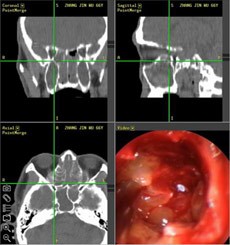

ΓΓΓΓ[‘≠άμ≤ϊ ω]: “”ΦΦ θ“‘“CTΤ§Φλ≤ι”ΚΆ“STORZ±«ΡΎΩζΨΒ”ΨΪΉΦΕ®ΈΜΘ§Ϋη÷ζ“ΟάΙζΟάΕΊΝΠΈΔ¥¥«–ΗνΕ·ΝΠœΒΆ≥”ΚΆ“ΟάΙζΫήΈςΈΔ¥¥ ÷ θœϊ»ΎœΒΆ≥” ΨΪ»Ζ“…®ΨΜ”ΥΡΕ‘±«ώΦ―Ή÷ΔΘ§±ήΟ⓬©’οΟΛ«χ”ΓΔ«®―”ΤδΥϋ±«ώΦΗ¥ΖΔΘΜΆ§ ±ΙΠΡή–‘±««Μ θΚσ–όΗ¥ΚΆ¬Χ…ΪΦΦ θΘ§«αΥ…«ε≥ΐΕνώΦΓΔ…œρΔώΦΓΔ…ΗώΦΚΆΒϊώΦΒ»Κœ≤Δ÷ΔΘ§―ΗΥΌΜ÷Η¥±«≤ΩΙΠΡήΘ§÷ΈΝΤΜ÷Η¥ΤΎ±»Ά§Β» ÷ θΥθΕΧ»ΐ±ΕΘ§±Μ≥ΤΈΣ“ΕύώΦ“Μ«ε”ΗΏΕΥΦΦ θΓΘ

ΓΓΓΓ”≈ Τ1Θ§ΨΪ»ΖΕ®ΈΜΘΚ “ΙΠΡή–‘±«ΡΎΩζΨΒœΒΆ≥”Ή‘¥χΒΡάδΙβ‘¥ΒΡΝΝΕ»œύΒ±”ΎΈό”ΑΒΤ20±ΕΘ§«εΈζΒΡ ”“Α Ι÷ΈΝΤ¥οΒΫΗϋΨΪœΗΒΡ–ßΙϊΘ§3.5mmΒΡ–ΓΩΉΩ…ΫΪ≤Γ±δΉι÷·Ζ≈¥σ ΐ±ΕΘ§≤ΔΫΪΆ§≤Ϋ≈Ρ…ψΒΫΒΡ”Αœσ¥ΪΥΆΒΫœύ”ΠΒΡΒΡΒγΡ‘ΤΝΡΜ…œΘ§ΜΦ’Ώ≤Γ±δ≤ΩΈΜΩ…±Μ“Ϋ…ζ“ΜάάΈό”ύΘ§Ω…Ηφ±πΙΐ»ΞΟΛΡΩΤΨ ÷Η–ΚΆΨ≠―ι≤ΌΉςΒΡ“ΟΛ»ΥΟΰœσ” ±¥ζΓΘ

ΓΓΓΓ”≈ Τ2Θ§ΈΔ¥¥ΨΪΟήΘΚΟάΙζΟάΕΊΝΠΈΔ¥¥«–ΗνΕ·ΝΠœΒΆ≥Θ§«ΩΒςώΦΩΎ±«ώΦΗ¥ΚœΧεΉη»ϊΕ‘¬ΐ–‘±«ώΦ―ΉΖΔ≤ΓΒΡ÷Ί“Σ≤ΩΈΜΫχ––“ΐΝςΘ§≈δΧΉ…ηΦΤ50Εύ÷÷ΨΪœΗΈΔ–ΓΒΫΦΗΚΝΟΉΒΡ–ΓΒΕΆΖΘ§Ρή‘Ύ’≠–ΓΒΡ±««ΜΓΔ― ΚμΆ®ΒάάοΝιΜν‘Υ”ΟΘ§ Βœ÷”––ß«ε≥ΐ≤ΔΦ¥ ±≥ιΈϋ≈≈≥ω≤ΜΝτ≤–”ύΘ§Φθ…ΌΗ¥ΖΔΒΡΡΩΒΡΘ§Φ¥“–ΓΖΕΈß÷ΈΝΤΫβΨω¥σΖΕΈß≤Γ±δ”ΓΘ

ΓΓΓΓ”≈ Τ3Θ§Ά¥Ωύ–Γ÷ΈΝΤΘΚ±«ΡΎΩζΨΒœ¬Ά®≥Θ Ι”ΟΟάΙζJ.CΘ®ΫήΈςΘ©ΈΔ¥¥ ÷ θ»»ΟτΦΦ θ÷ΈΝΤΘ§Ε‘≤Γ±δΉι÷·œϊ»ΎΒΡ“Μ÷÷ΗΏΩΤΦΦΒΡ÷ΈΝΤ ÷ΕΈΘ§”κ¥ΪΆ≥ΦΛΙβΈΔ≤®÷ΈΝΤΗΏ¥ο150ΓφΒΡΈ¬Ε»œύ±»Θ§ΦΪ¥σΒΡΦθ«αΝΥΉι÷·ΒΡΥπ…ΥΚΆ≤Γ»ΥΒΡΆ¥ΩύΓΘ

ΓΓΓΓ”≈ Τ4Θ§÷ΈΝΤΑ≤»ΪΘΚ»ΐ¥σ «Α―Ί’οΝΤœΒΆ≥ΚœΝΠΘ§ΨΪ»Ζ…®ΨΜ≤Γ±δΉι÷·Θ§±ήΟβΙΐΕύΥπ…ΥΘ§ΫΪΗ±Ής”ΟΫΒΒΫΫœΒΆΘ§≤ΜΫωΦ”¥σΝΥΑ≤»Ϊ–‘Θ§Ά§ ±“≤ΥθΕΧΝΥ3±ΕΜΦ’Ώ θΚσΒΡΜ÷Η¥ ±ΦδΓΘ